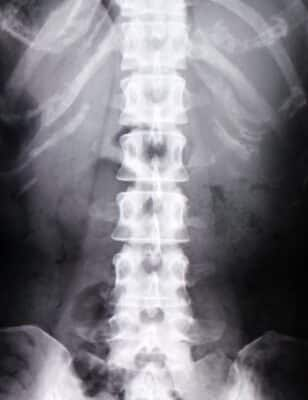

ぎっくり腰・捻挫・リハビリ・アキレス腱断・椎間板ヘルニア・脊柱管狭窄症・変形性股関節・膝関節症にも対応可能 茨城県牛久市で接骨院、整骨院をお探しなら蛯原接骨院へ